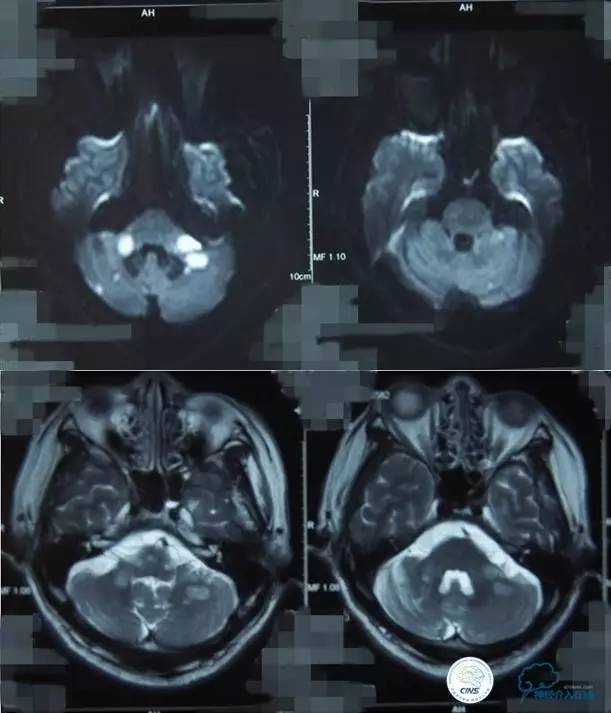

▼影像学资料

入院后,患者症状稍有加重,出现走路不稳,查体发现两手指鼻不稳。行颅脑MRI检查。给予双抗血小板、调脂、改善脑循环、营养神经等药物治疗。立普妥20mg qn。实验室检查:LDL-C:3.31mmol/L。

▼颅脑CT灌注扫描